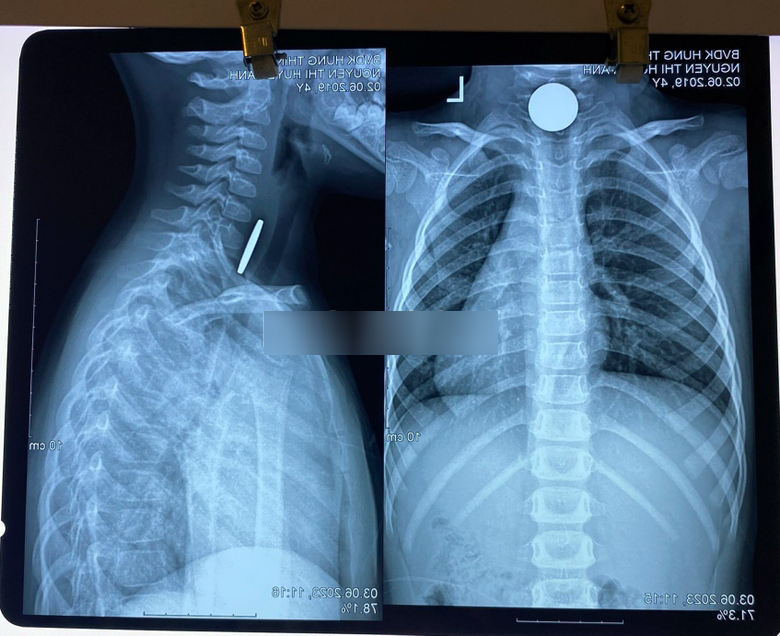

Theo gia đình bệnh nhi này, bé ở nhà chơi và nghịch nuốt 1 đồng xu. Ngay sau đó, Bệnh viện Đa khoa Hưng Thịnh tiếp nhận trẻ, sau đó được chụp X-quang chẩn đoán, kết quả cho thấy dưới cơ thắt nhãn hầu có dị vật là 1 đồng xu.

Hình ảnh chụp X-quang cho thấy dị vật tại thực quản của trẻ. (Ảnh: Báo Lào Cai).

Các bác sỹ đã hội chẩn và chỉ định thực hiện gây mê, gắp dị vật thực quản qua nội soi bằng kìm cá sấu. Đồng xu được gắp ra thành công có đường kính khoảng 4 cm, sức khỏe trẻ hồi phục tốt.